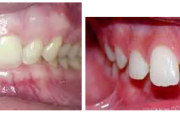

Normaalse jäävhammaskonna pilt küljelt ja eest vaadatuna.